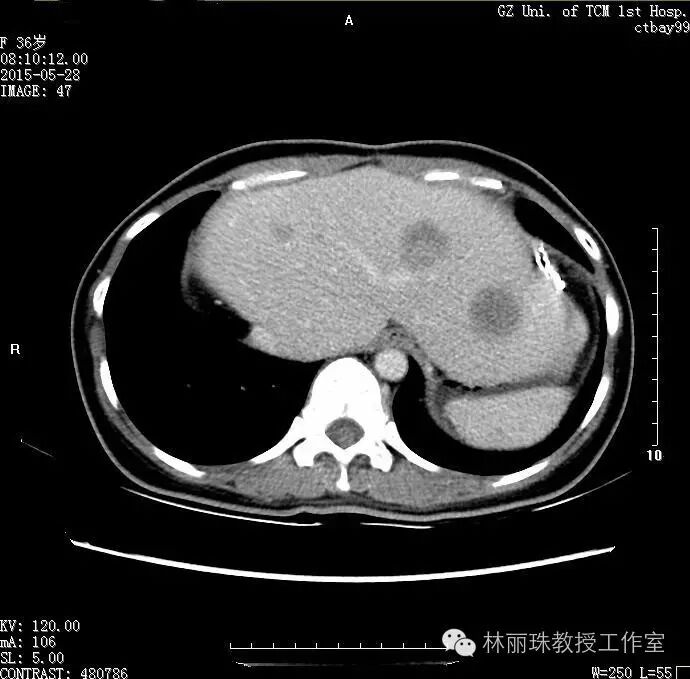

2015812日复查CT提示残肝肿大,其内见多发结节及肿块影,较前明显增大,最大者位于左外叶上段(大小约9.6cm×4.4cm),腹膜后见多发小淋巴结影(最大直径11mm),双肺可见多发散在微小结节(直径约4~5mm)。遂于2015-8-29开始于原化疗方案配合贝伐珠单抗治疗共8程(末次化疗2016325日)。2016328日复查CT:残肝多发转移瘤较前明显缩小(5.3cm×1.4cm),左叶外侧段肿瘤放射粒子植入术后基本坏死,腹腔多发小淋巴结基本同前(1.1cm);双肺多发微结节(4~5mm),较前变化不大。后患者持续门诊中药治疗至今。2016617日复查CT示肝内多发转移瘤与3CT所见大致相同。

20155月复查,可见肝内出现肿瘤复发